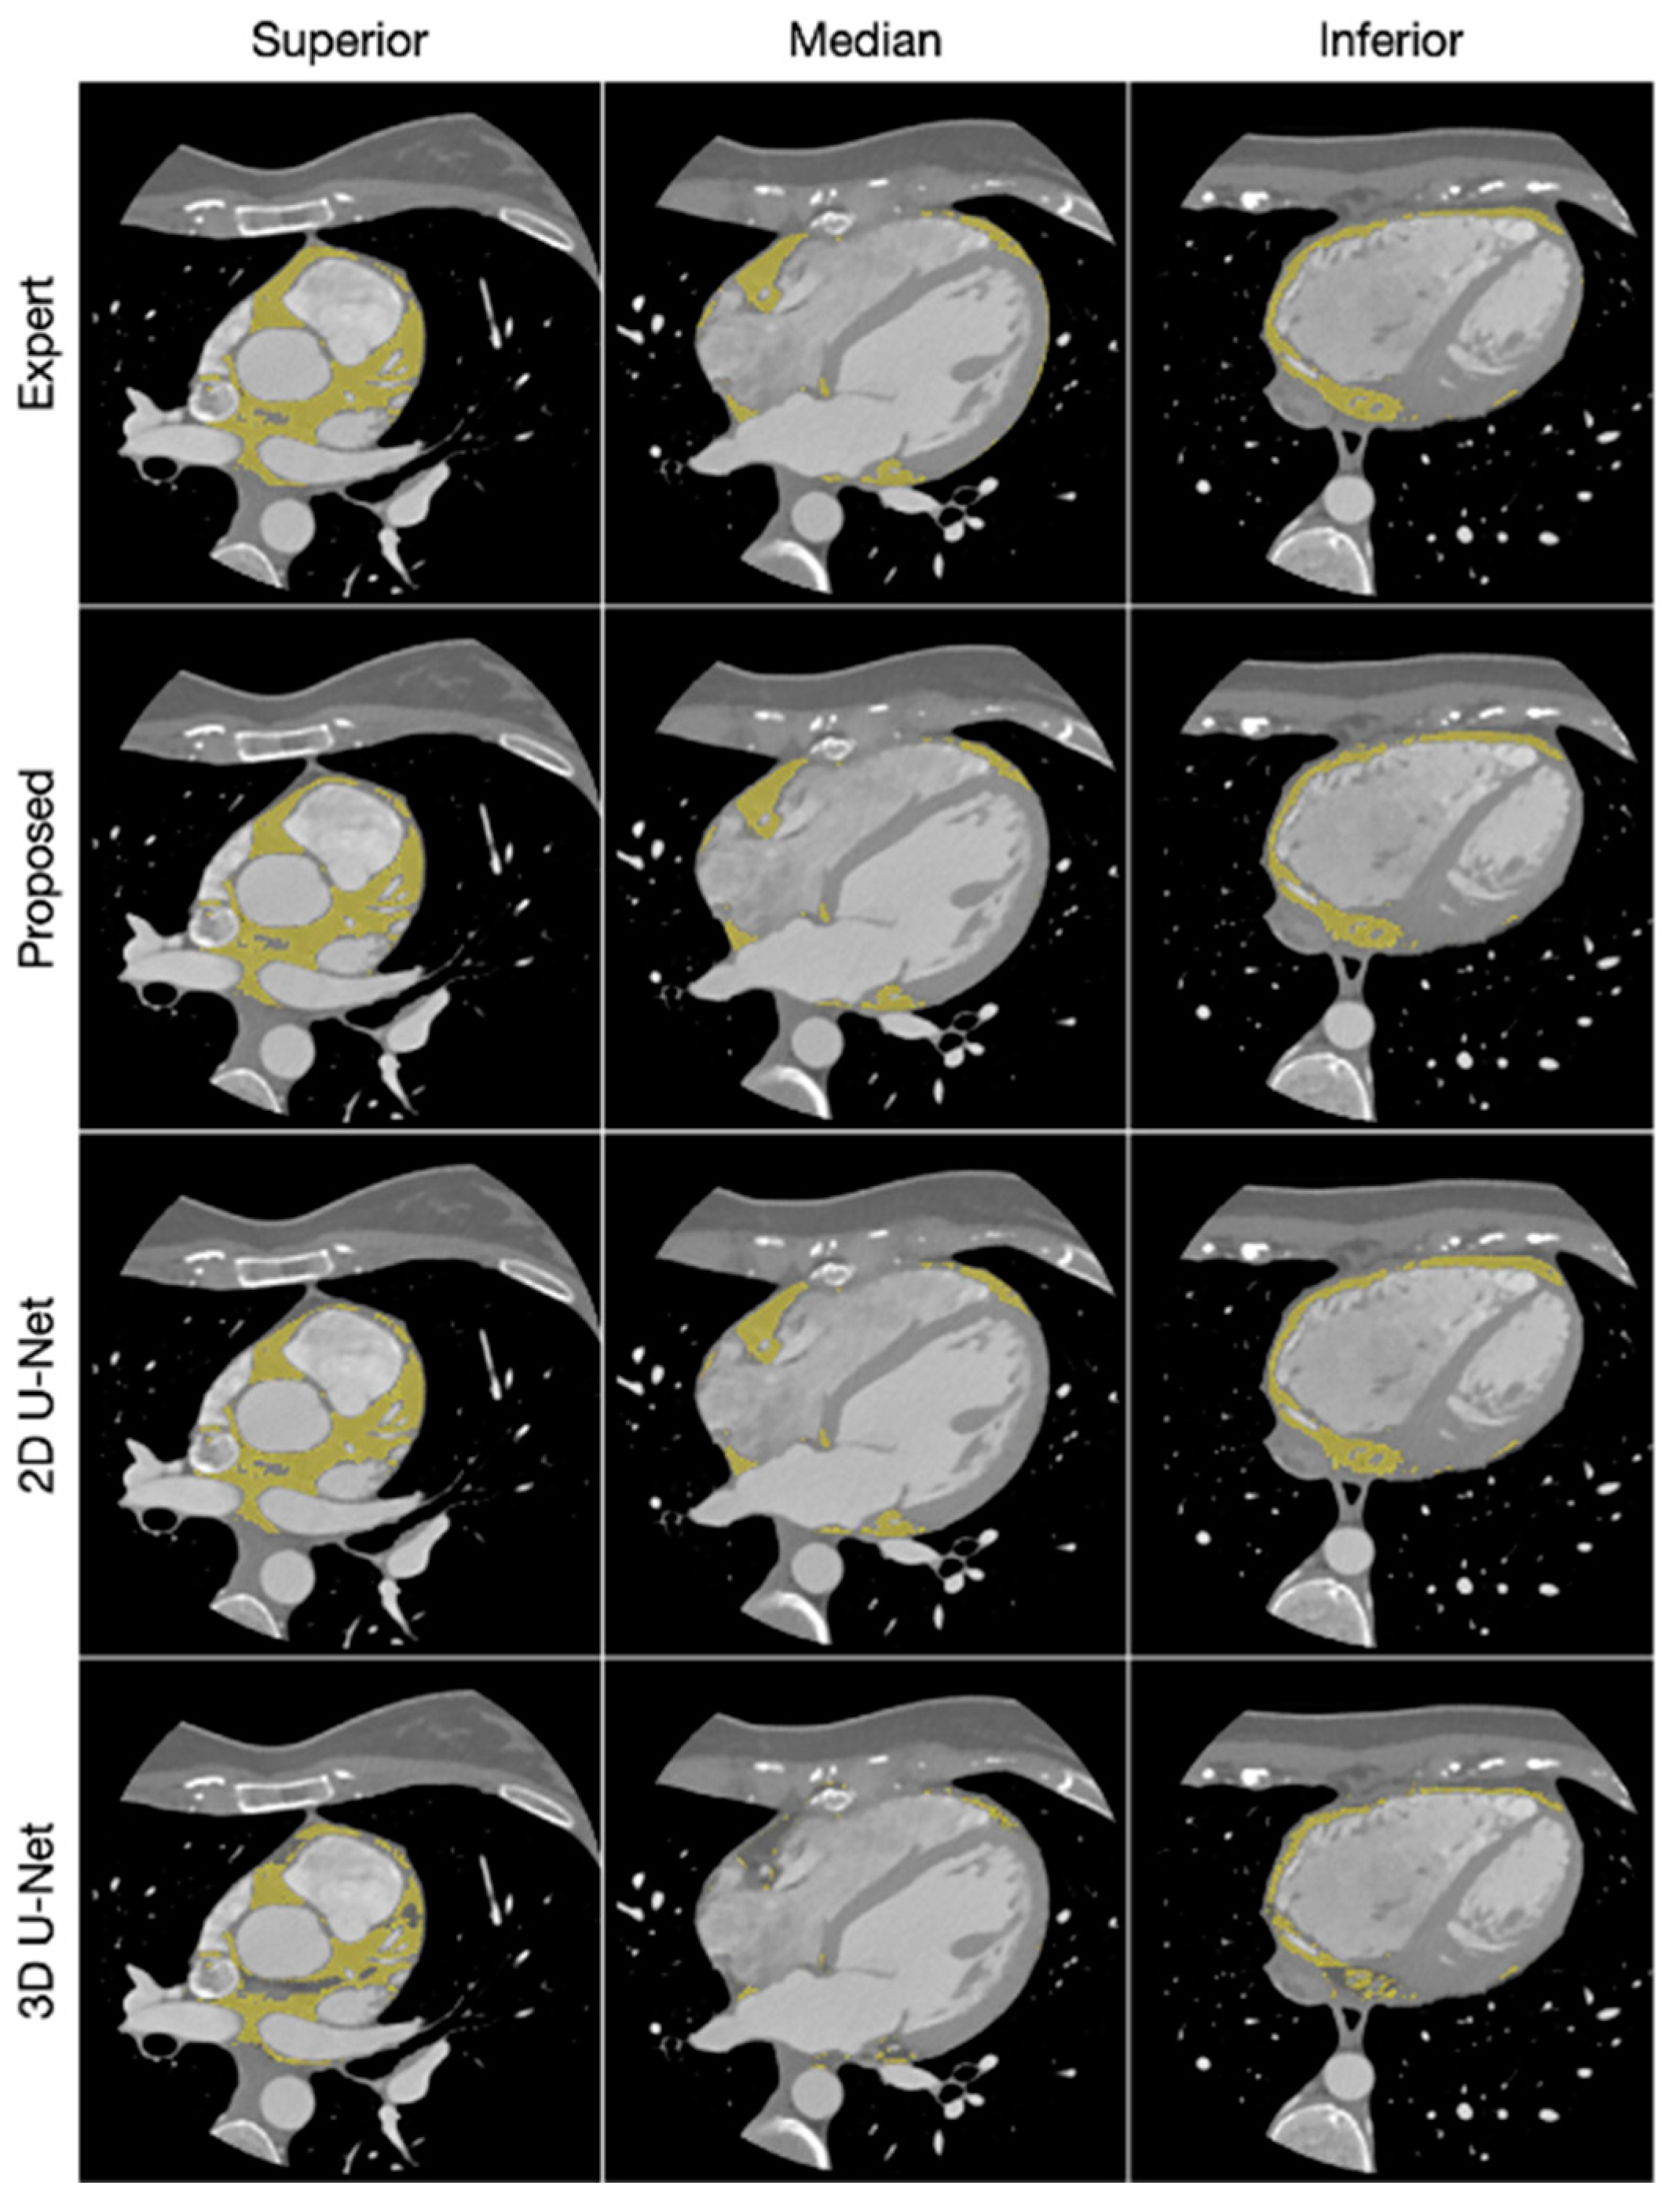

- Kulasekara M, Dinh VQ, Fernandez-del-Valle M, Klingensmith JD. Comparison of two-dimensional and three-dimensional U-Net architectures for segmentation of adipose tissue in cardiac magnetic resonance images. Med Biol Eng Comput. 2022;60(8):2291-2306. [CrossRef]